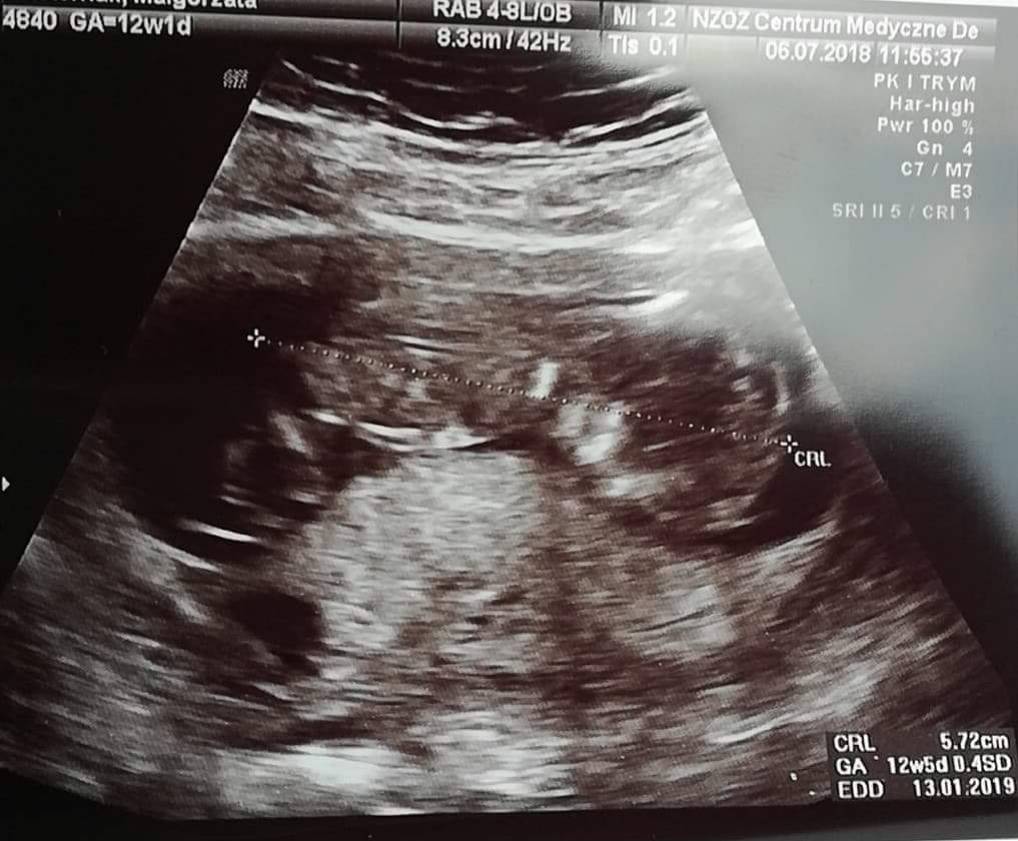

Ja już po badaniu prenatalnym. Na USG wszystko wyszło ok, serduszko, żołądek, kość nosowa i karkówka, także nie ma powodu do zmartwień. Maleństwo ma już 5,7 cm niestety dupci nie chciało pokazać i o płci nie było szans porozmawiać [emoji7]

IMG_20180706_141604.jpg